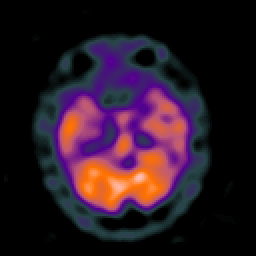

Huntington's Chorea, MR -- Slice #5

[Home][Help][Clinical] Slice 5